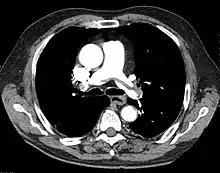

At the bedside, point-of-care echocardiography should be used.[29] This is non-invasive and can help diagnose the four types of shock.[31] Echocardiography can look for ventricular dysfunction, effusions, or valve dysfunction.[3][32] Measurement of the vena cava during the breathing cycle can help assess volume status.[29][31] A point-of-care echocardiogram can also assess for causes of obstructive shock. The vena cava would be dilated due to the obstruction. In pulmonary embolism, the right ventricle will be dilated. Other findings include paradoxical septal motion or clots in the right heart or pulmonary artery. Echocardiography can assess for pericardial effusion. In tamponade, collapse of the right atrium and ventricle would be seen due to pressure in the pericardial sac.[31]

A chest X-ray can rapidly identify a pneumothorax, seen as absence of lung markings. Ultrasound can show the lack of lung sliding. However, imaging should not delay treatment.[8] CT angiography is the standard of diagnosis of pulmonary embolism. Clots appear in the vasculature as filling defects.[18]